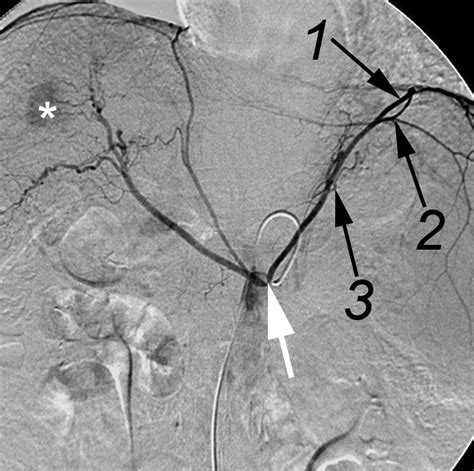

The origin of the Inferior Phrenic Artery is characterized by significant anatomical variability, which is a point of frequent discussion in medical literature. Typically, the right and left IPAs arise either independently from the abdominal aorta, immediately superior to the celiac trunk, or as common trunks from the aorta or celiac artery itself.

Because of this proximity to major visceral arteries, the IPA serves as a vital collateral pathway. When other primary blood vessels, such as the celiac artery or mesenteric arteries, become stenotic or occluded, the IPA can undergo hypertrophy to compensate for the reduced blood flow, effectively acting as a bypass channel for the foregut organs.

Detecting the Inferior Phrenic Artery can be difficult if the vessel is small or if the patient has significant atherosclerosis. Advanced software in modern angiography suites now allows for 3D reconstruction, which drastically improves the visualization of these small vessels. By overlaying pre-procedural CTA onto the live fluoroscopic image, surgeons can more accurately locate the ostium of the IPA, significantly reducing the time spent searching for the vessel and decreasing the total radiation dose to the patient.